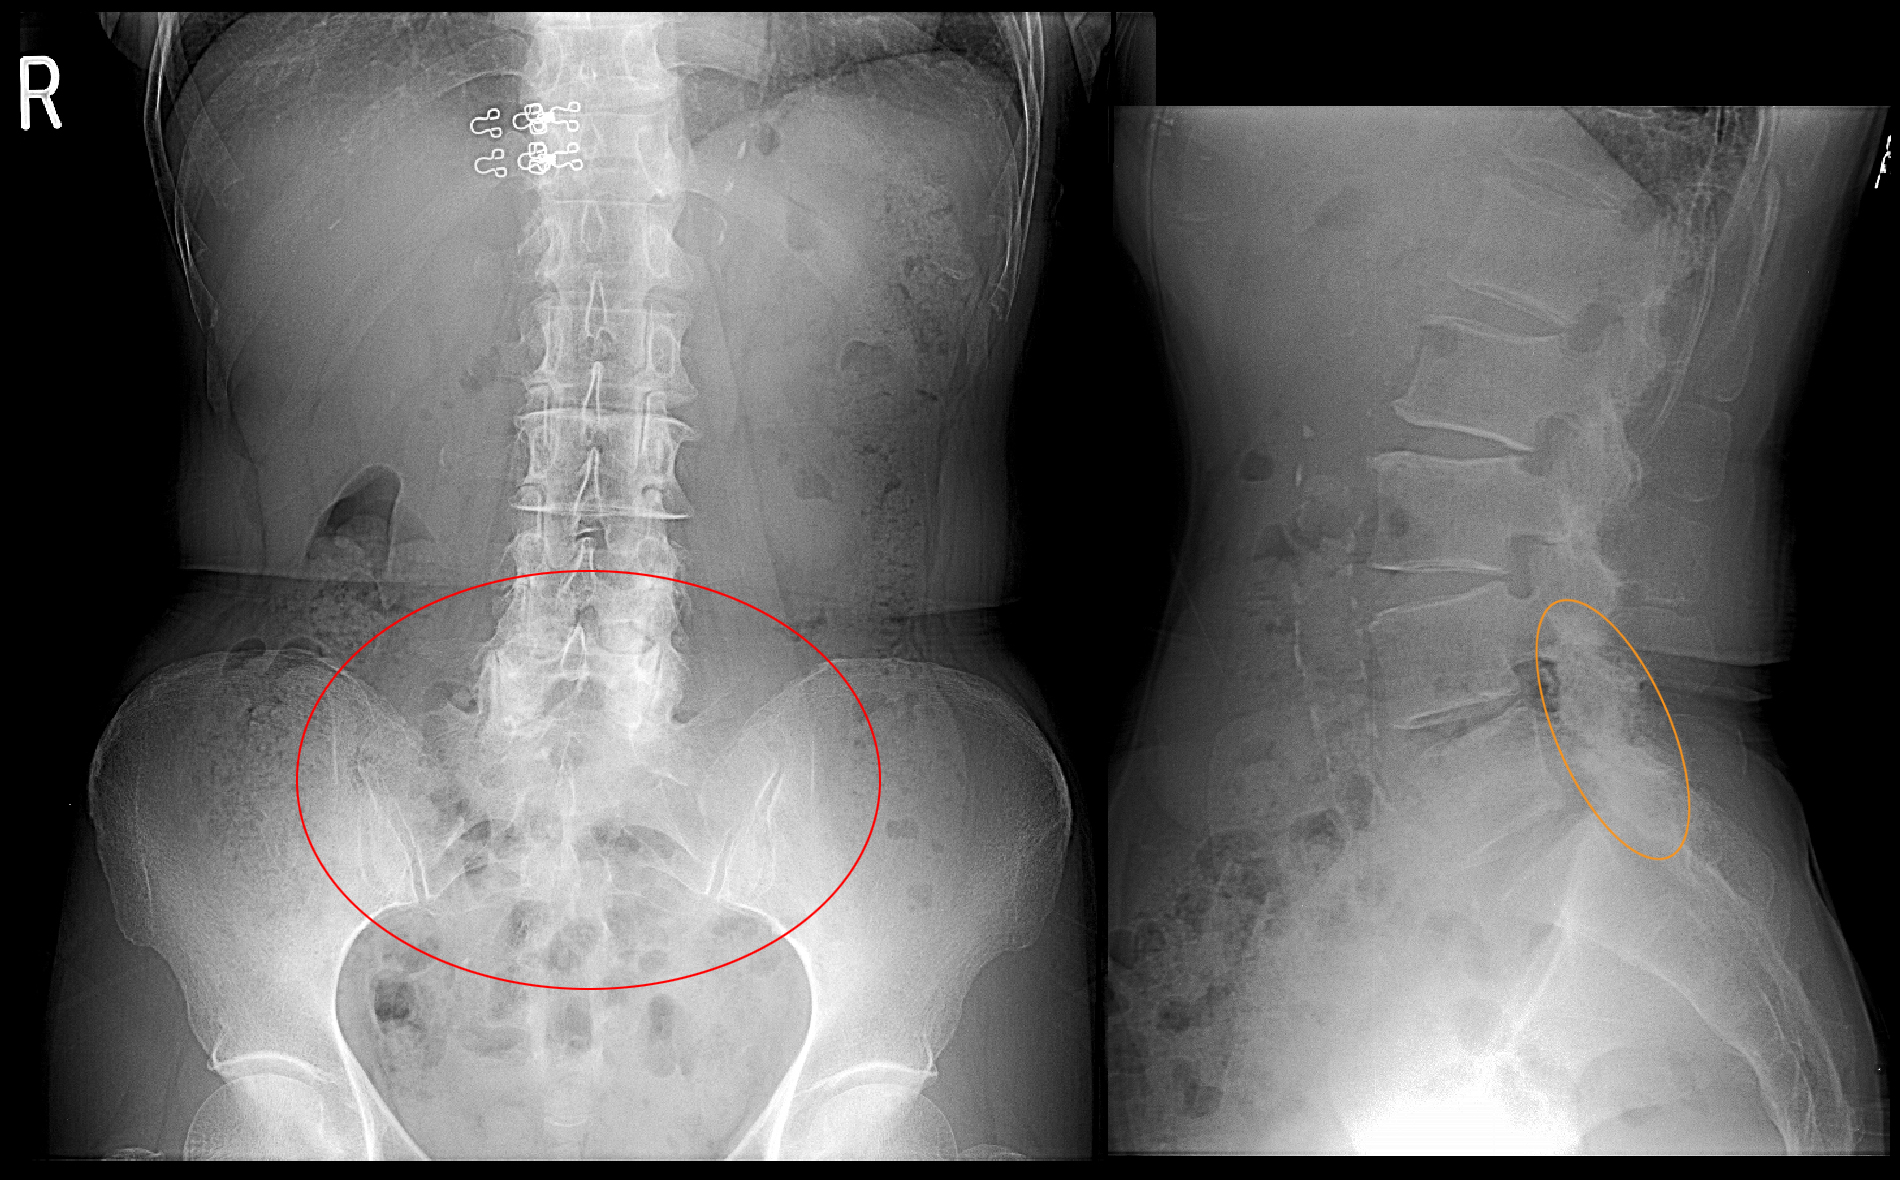

73才女 Xp.jpg

レントゲン像ではL4・L5の椎体の後方部分(椎弓といいます)が白っぽくなっており(オレンジ丸領域です)、老化よるによる椎弓部が骨肥厚を起こしていると推察し、同部での脊髄の圧迫による腰痛であろうと予測しました。